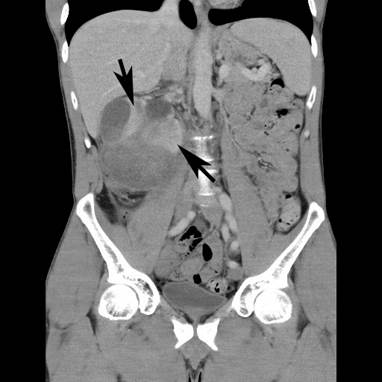

A 43-year-old Caucasian man, with a 4-week history of right upper quadrant and right flank pain radiating to his right testicle, presented to his general practitioner. There was no preceding trauma, haematuria or any other systemic symptoms. The past medical history included osteoid osteoma in the left upper femur, which was removed in 2007. He also had L4/5 microdiscectomy. There was no positive family history of medical problems or cancer. He was a non-smoker, had no allergies and was not taking any regular medications. The general practitioner organized an ultrasound, which revealed a large subcapsular haematoma measuring 7 × 5 × 7 cm in the right kidney compressing the renal cortex. Further investigation with computed tomography (CT) scan of the abdomen with intravenous contrast revealed enlarged right kidney with subcapsular haematoma and a mass lesion within the right lower pole measuring up to 7.4 × 7.5 × 9.2 cm with associated paracaval lymphadenopathy producing compression of the right renal vein and inferior vena cava (Figures 1 and 2). The patient was then referred to an urologist for further management.

Figure 2

Figure 2. CT scan – coronal view showing right kidney mass with subcapsular haematoma (arrows).